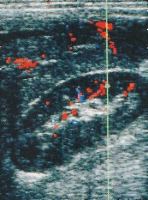

Vaskulär verursachte Abstoßungen können neben immunologisch bedingter Arterienstenose auch nahttechnisch verursacht sein. Angiodynographische bzw. angiographische Abklärung ist erforderlich, evtl. anschließende Angioplastie. Die Angiodynographie stellt ein wichtiges diagnostisches Verfahren zum Nachweis der Durchblutung des Organs im postoperativen Verlauf dar (Abbildung 9).

Das Verfahren benötigt kein Kontrastmittel bzw. Röntgenstrahlen und ist damit insbesondere bei Kindern und Jugendlichen angezeigt.

Zur Kontrolle der Nierenfunktion bzw. Durchblutung ist auch ein Nierenfunktionsszintigramm (NFZG) geeignet. Glomerulär filtrierte Substanzen eignen sich für die Funktionsbeurteilung von transplantierten Nieren. Sie werden dann bevorzugt, wenn Blutfluss und glomeruläre Filtrationsraten zu bestimmen sind

Literatur:Zwirewich, Ch.: "Sonography of Normal Renal Transplants" in Renal Transplant Imaging and Intervention: Practial Aspects - 2", Vancouver Hospital &Health Sciences Centre, Vancouver, 1998.